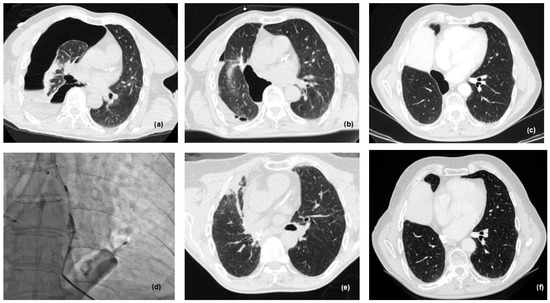

2.3. New Therapeutic Horizons: Percutaneous Treatment of Small and Late BPF